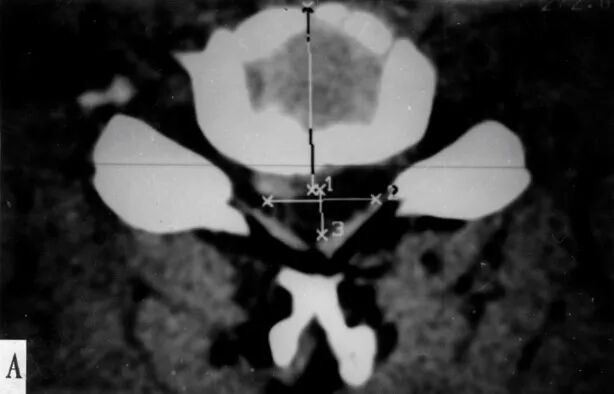

CT扫描从颈椎横断切层显示椎管、脊髓及其相互关系

颈椎病CT表现